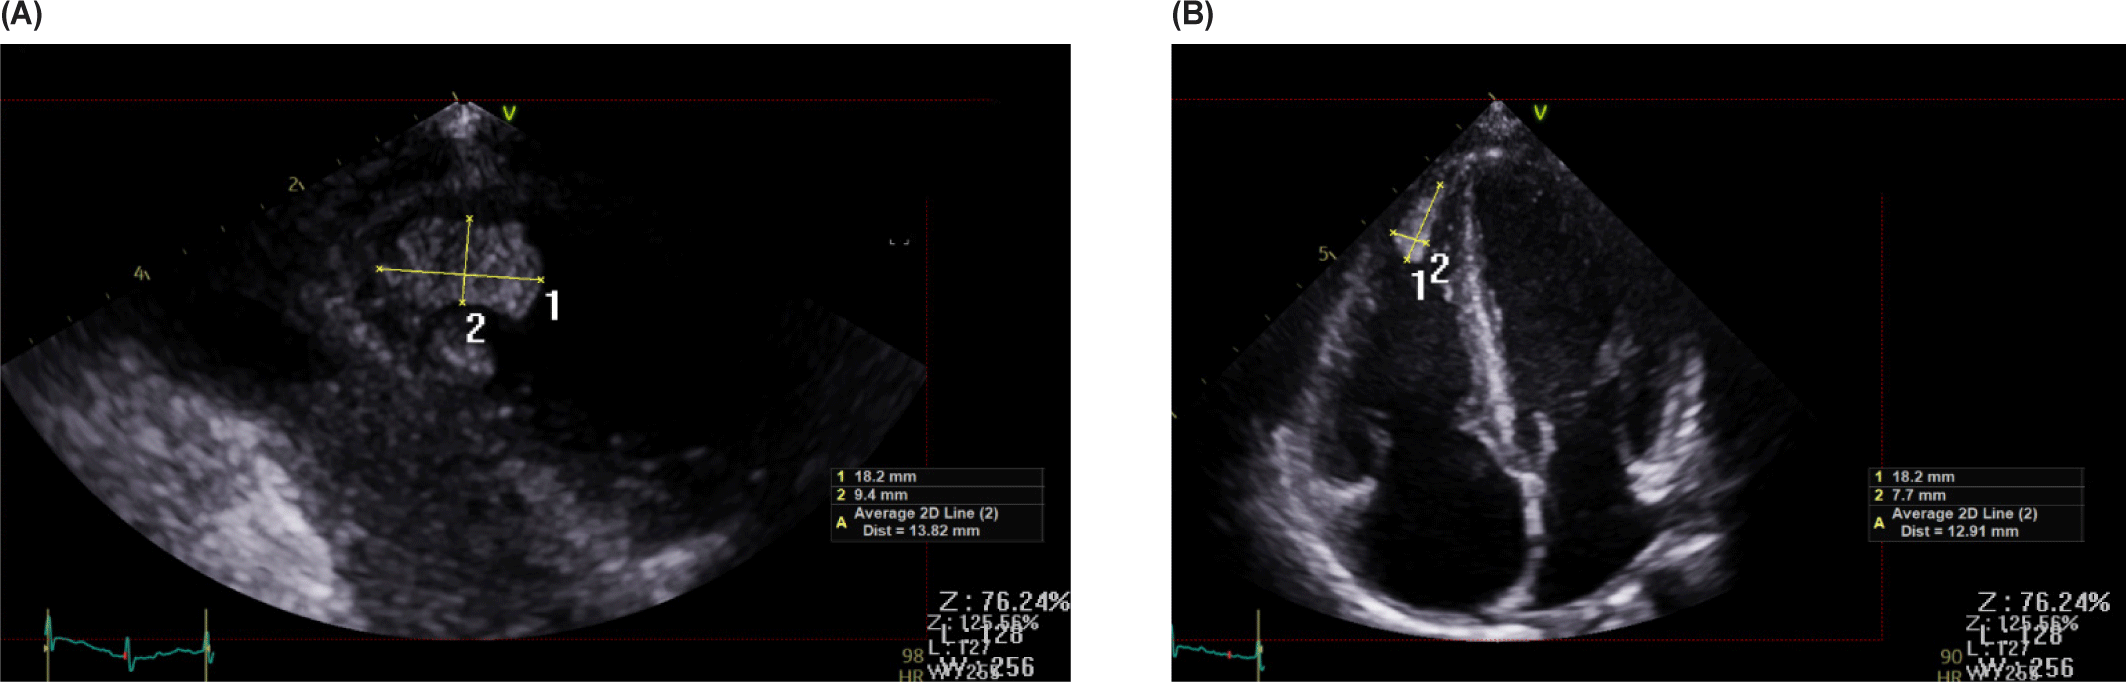

Laboratory tests showed a prolonged prothrombin time (INR 1.34) and elevated inflammatory markers, including C-reactive protein (CRP, 46.4 mg/L), procalcitonin (0.52 ng/mL), and serum amyloid A (SAA > 300 mg/L). Cardiac biomarkers were markedly elevated, with an NT-proBNP level of 1,616 pg/mL. A respiratory pathogen panel detected rhinovirus A/B, metapneumovirus, Mycoplasma antibodies, and SARS-CoV-2 antibodies. Echocardiography revealed reduced left ventricular (LV) systolic function (ejection fraction 43%) while right ventricular (RV) function remained preserved. No coronary artery dilation, thrombus, or infarction was identified on echocardiography (Fig. 1).

Fig. 1. Echocardiographic findings of Case 1. Transthoracic echocardiography demonstrated reduced left ventricular systolic function with a left ventricular ejection fraction (LVEF) of 43%, while right ventricular function was preserved. No coronary complications were identified.